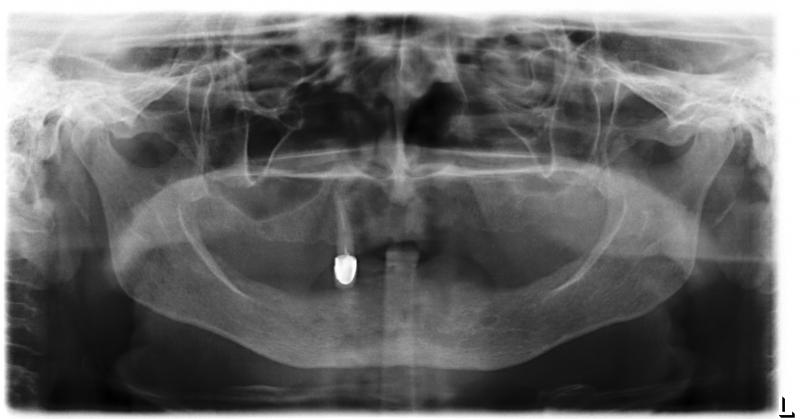

Фото →Установка 10 имплантантов на беззубую челюсть с помощью компьютерной программы: Первый визит пациентки